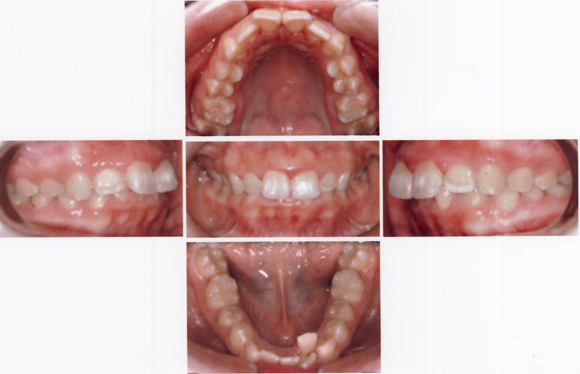

CASE4 乱杭歯(歯がひどく不揃いに生えている:八重歯や叢生も含む)ケース

術前

術後